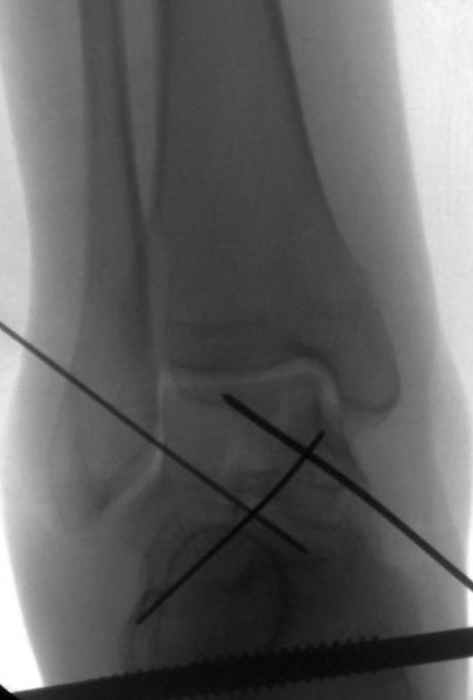

Вдогонку по поводу перелома таранной кости, больная 81, не страдает диабетом, перелом закрытый, в первый же день поступления ограничились временным наружным фиксатором (как на снимке).

Из-за отека на стопе тактика лечения у всех была

одинаковая: временная наружная фиксация до спадения отека, при изолированных переломах они выписывались домой и через дней 7 госпитализировались на оперативное лечение.

Примеры на снимке...